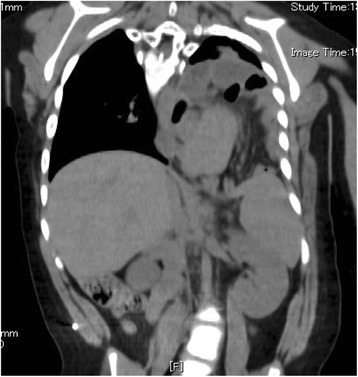

A CT scan revealed the herniation of the large and small intestine into the thoracic cavity; we were therefore of the opinion that they should be pulled down into the abdominal cavity in order to resolve the patient’s respiratory problems (Fig. 1). We thought that we should perform tracheotomy or laryngotracheal separation before repairing the recurrent hiatus hernia because the patient presented with severe dysphagia as well as severe hiatus hernia. An upper gastrointestinal series and endoscopy were performed to evaluate the esophagus and stomach, revealing the presence of residual gastroesophageal reflux and an elevated esophagus due to the recurrent hiatus hernia.

Fig. 1.

A CT scan revealed the herniation of the stomach and the large and small intestine into the thoracic cavity